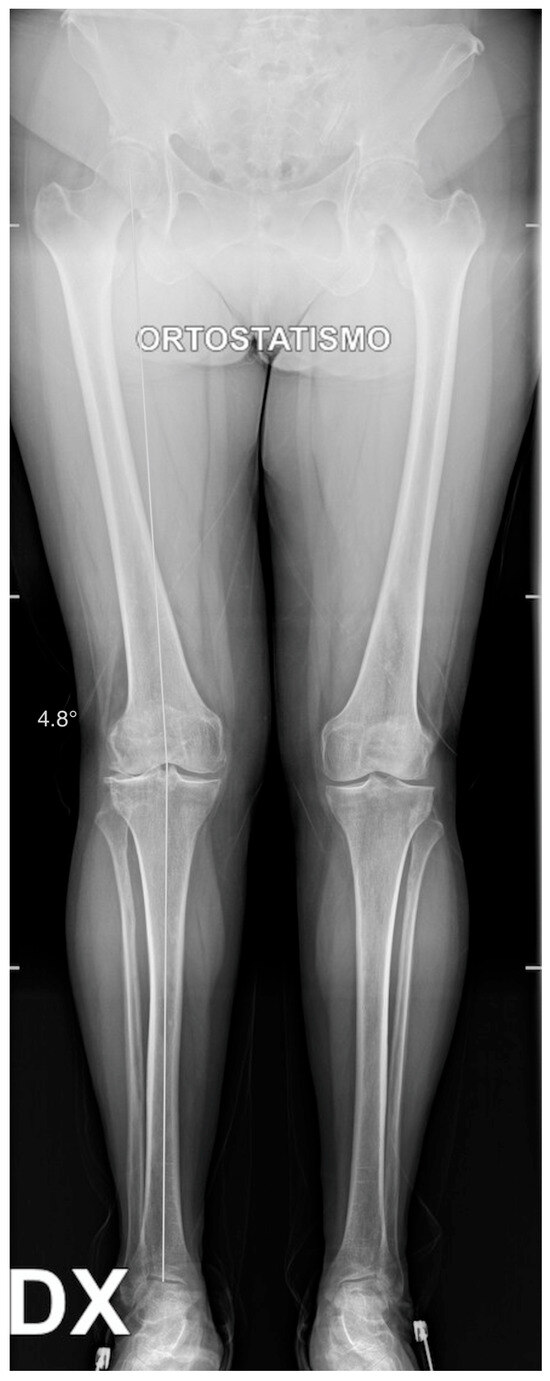

One-Stage Tricompartmental Hypoallergenic UKA for Tricompartmental Osteoarthritis: A Case Report

2. Case Description